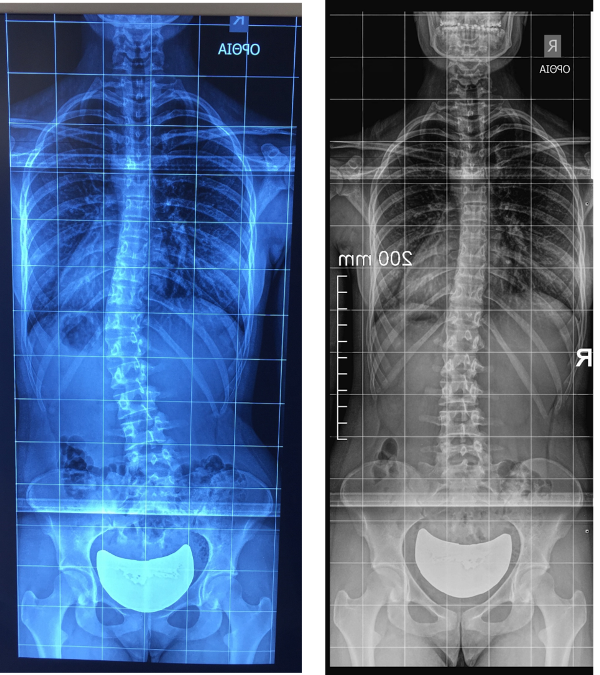

Η πρόσφατη ακτινογραφία της Άννας (09-2016), 7 μήνες μετά την εφαρμογή των ασκήσεων της μεθόδου Schroth-BSPTS, φανέρωσε μια εντυπωσιακή ακτινολογική βελτίωση 15 μοιρών, καθώς η γωνία Cobb πλέον είναι στις 10 μοίρες, από τις 25 μοίρες αρχικά. Η εμφάνιση της κοπέλας, όπως ξεκάθαρα φαίνεται στην παραπάνω φωτογραφία, βελτιώθηκε σημαντικά και το σώμα της έχει μια απόλυτη συμμετρία. Επίσης, η κλινική εξέταση με το σκολιώμετρο φανέρωσε μια εξίσου σημαντική διόρθωση της στροφής των σπονδύλων, από τις 12 μοίρες αρχικά στις 6 μοίρες.